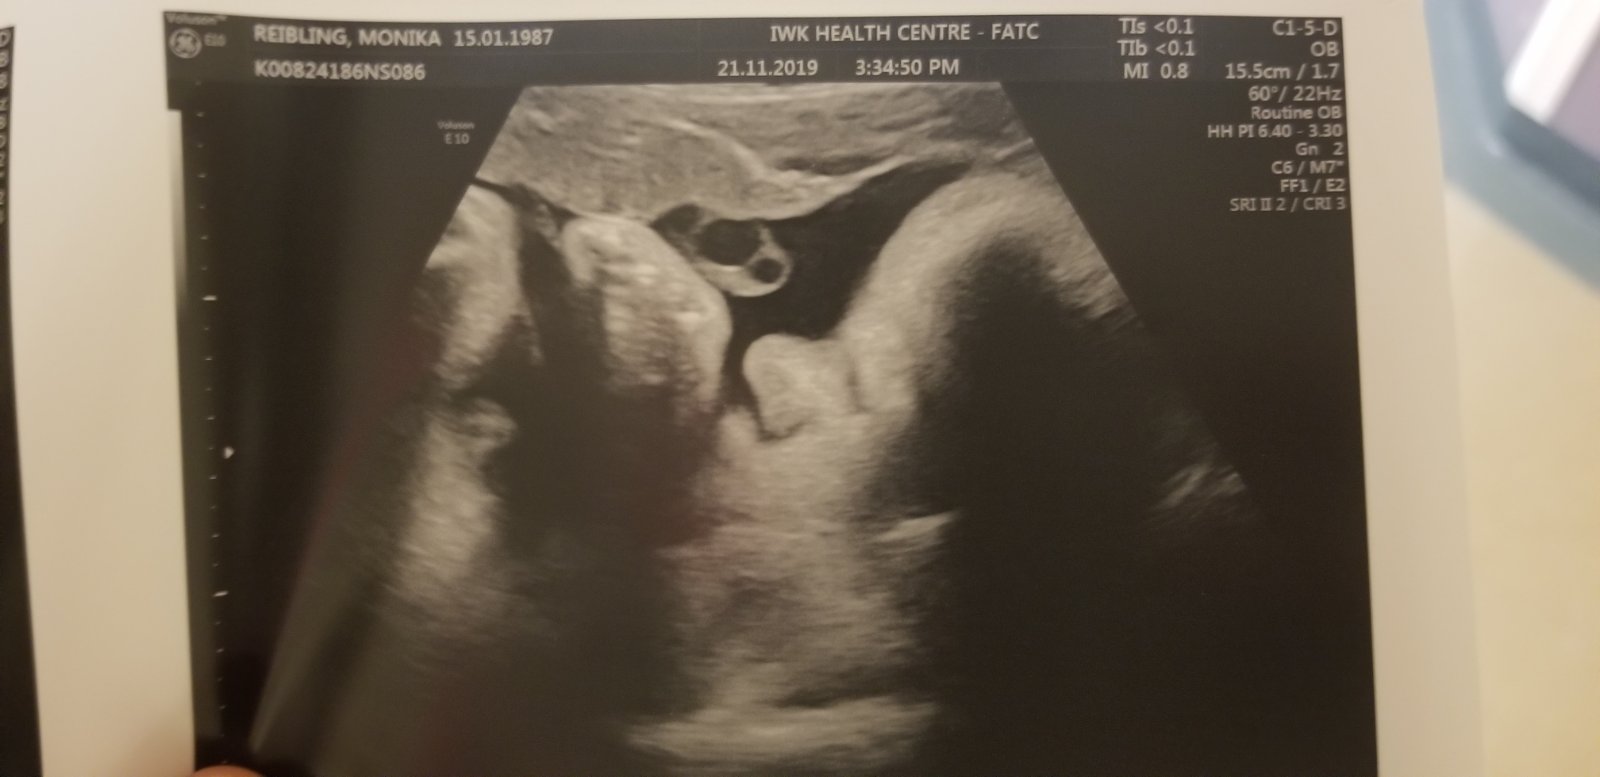

Ja mam termin 17.12 alebo 19.12 dufam ze to bude niekedy vtedy alebo pred 🙂 zatial to este nevyzera, som v 36 +4tt je otocena dole hlavou ale este je tak vyssie, nezosunula sa este, visc menej je na pol ceste :D mala som kontrolu vo stvrtok a vsetko oki 🙂 este aj fotecka sa nam podarila 🙂 uz sa moc tesim, ale aj panika ma chyta trosku z porodu a tak vsetkeho. Mate uz vsetko nakupene, pochvalte sa s kocickami a izbickami a babatkami ked budu 😊😍 fotecky su stvrtok a v 26tt 3d sono 🙂